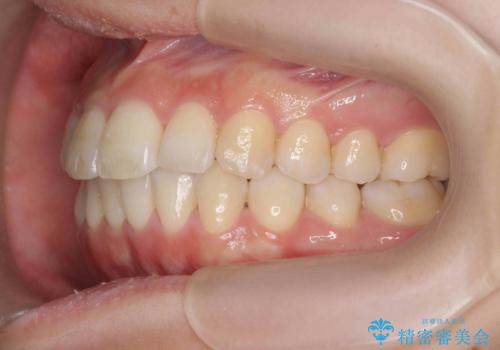

インビザラインで出っ歯の治療

- 「目立つ前歯の出っ歯をなんとかしてほしい。」と矯正治療を希望され来院されました。

突出した上顎の前歯に加え、ガタつきの目立つ下顎の歯列も同時にマウスピース矯正インビザラインで整えていきます。

突出間(所謂 出っ歯)のある前歯の位置は大幅に改善され、審美性が大きく向上しました。

加えて奥歯も噛み合わせも良くなったことで、咬合状態が安定しより安定した歯列を獲得することができました。